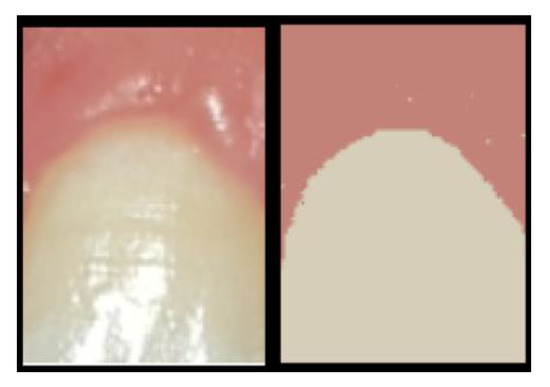

The 35 features were extracted using the following 3-step process; Step 1: separate the image into two regions—the tooth region and gum region (Figure 8). Step 2: image transformation to achieve normalization of colors and hues, and edge enhancement. Step 3: feature extraction from the resulting transformed image. We will now describe these three steps more closely.

Step 1: image separation into two regions–we used the K-mean clustering algorithm with K = 2 to separate the image into its two most prominent clusters (regions)—the gum region and tooth region. See Figure 8 for an example of separation into two clear and distinct regions.

Figure 8. Image separation into two regions—left: the original tooth image; right: the separation into two regions (clusters) produced by the K-mean algorithm.